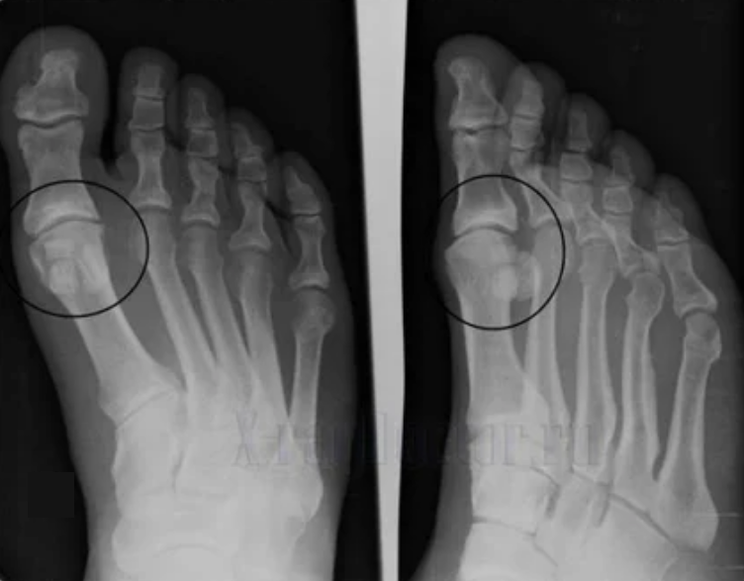

Lai veiktu diagnozi, reimatologi pēta pacienta sūdzības un izraksta x -ray pārbaudi. Visbiežāk radiogrāfija tiek izmantota 2 projekcijās. Ārsts aplūko distrofisku traucējumu klātbūtni hialīna skrimšļa un kaulu locītavās. Ja locītavu sprauga tiek samazināta, kauli tiek deformēti vai saplacināti, skrimšļa virsmā ir cistiski veidojumi, osteofīti ir acīmredzamas artrozes pazīmes. Pārbaudes laikā artroze norāda uz locītavas nestabilitāti: ir traucēta ekstremitāšu un subluksācijas ass.

Bieži vien X -Ray attēls nespēj sniegt pilnīgu informāciju par locītavas stāvokli. Rūpīgākai pētījumam tiek noteikta datortomogrāfija, tā ir efektīva kaulu pārbaudei. MRI biežāk izmanto mīksto audu izpētei.